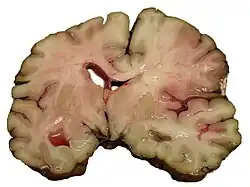

Einteilung nach Infarktmuster in der Bildgebung

Es kann zwischen Territorialinfarkten, Grenzzoneninfarkten und lakunären Infarkten unterschieden werden.

Territorialinfarkte entstehen durch embolischen Verschluss hirnversorgender Arterien und betreffen das Versorgungsgebiet (Territorium) des Gefäßes. Lakunäre Infarkte sind kleiner als 1,5 cm. Sie entstehen meist durch mikroangiopathische Veränderungen. Grenzzoneninfarkte sind hämodynamischer Genese. Sie entstehen meist durch Verschluss der großen extrakraniellen Gefäße oder durch einen passageren Blutdruckabfall bei vorbestehenden Einengungen der Halsschlagadern.[9]